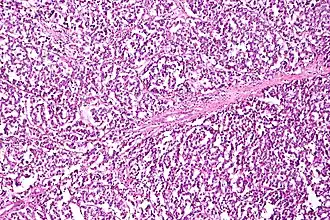

.jpg)

Serous ovarian cancer is the most common type of epithelial ovarian cancer and it accounts for about two-thirds of cases of epithelial ovarian cancer.[28] Low-grade serous carcinoma is less aggressive than high-grade serous carcinomas, though it does not typically respond well to chemotherapy or hormonal treatments.[28] Serous carcinomas are thought to begin in the Fallopian tube.[70][71] High grade serous carcinoma accounts for 75% of all epithelial ovarian cancer.[69] About 15–20% of high grade serous carcinoma have germline BRCA1 and BRCA2 mutations.[69] Histologically, the growth pattern of high grade serous carcinoma is heterogenous and has some papillary or solid growth patterns.[69] The tumor cells are atypical with large, irregular nuclei.[69] It has a high proliferation rate.[69] 50% of the time, serous carcinomas are bilateral, and in 85% of cases, they have spread beyond the ovary at the time of diagnosis.[72]